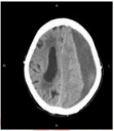

6. 女性 86 歲,近日來嗜睡,今早叫不醒,被送至急診室。家屬表示約 3 週前曾經跌倒, 頭部雖有撞到傢俱,但無明顯外傷。目前腦部電腦斷層檢查結果如下圖,病人最可能的診斷為何?(A) 腦內出血(B) 硬腦膜上血腫(C) 硬腦膜下血腫(D) 蜘蛛網膜下腔出血